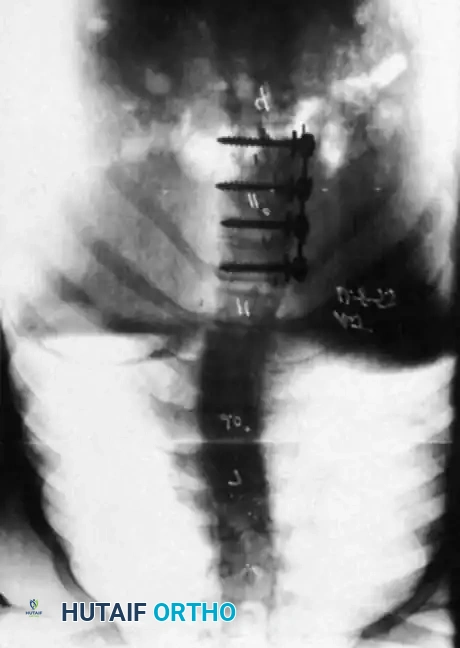

Associated Surgical & Radiographic Imaging

Hutaifortho's Orthopaedic Diagram